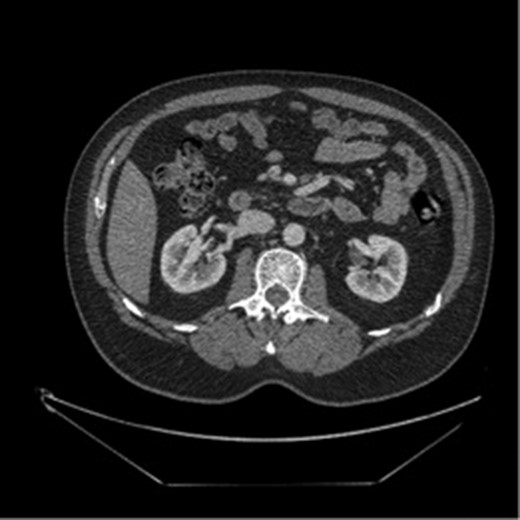

The patient was a 49-year-old male with history of hypertension presenting for evaluation for sudden onset of bilateral lower quadrant abdominal pain, nausea, emesis and non-bloody diarrhea starting 4 h prior to presentation. The patient denied prior abdominal surgeries, tobacco or illicit drug use. His history included hospitalization a year earlier for painless rectal bleeding, concerning for ischemic colitis, which was managed non-operatively. Current medications included Aspirin 81 mg and Valsartan-HCTZ. Physical exam revealed only mild left lower quadrant tenderness, and the labs values were quite unremarkable. A CT scan of the abdomen and pelvis with intravenous contrast demonstrated a thrombosed dissection, originating 2 cm from the ostium of the SMA with extension into the second and third order branches (Figs 1 and 2).

Initial imaging showing a thrombosed dissection, originating 2 cm from the ostium of the SMA with extension into the second and third order branches.

Repeat CT imaging 3 months after this hospitalization continued to show the SMA dissection with resolution of the SMA thrombus (Fig. 2). His warfarin was discontinued in exchange for a dual antiplatelet therapy.